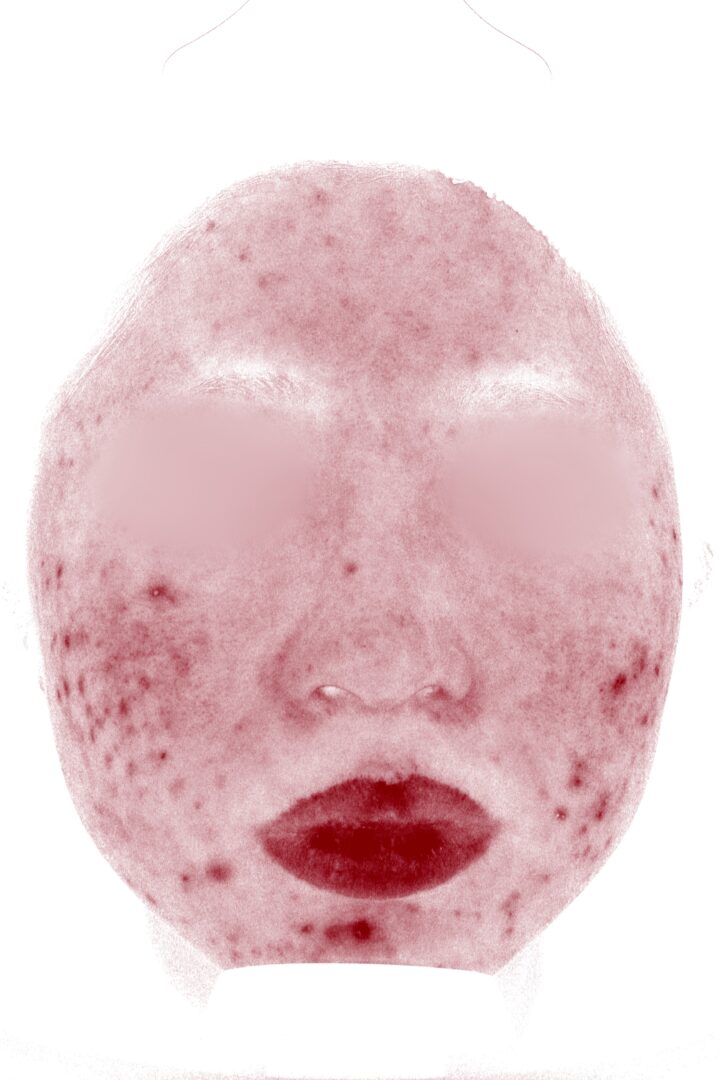

| 施術名 | ケミカルピーリング6回・ライムライト3回・ケアシス27回・内服薬・外用薬 |

| 医師 コメント | 小学校高学年頃からニキビに悩まされていた患者様です。 中学・高校時代には症状が強く、これまで保険診療で治療を続けてこられましたが、社会人になった現在もニキビが繰り返しでき、特にニキビが治った後に残る赤みがなかなか引かないことを気にされ、来院されました。 実際に、VISIAによる肌分析を行ったところ、赤み解析(Before)で濃い赤色の反応が顔全体にまだらに分布していることが患者様のお悩みの通り確認できました。VISIAの赤み分析は、皮膚の血液中に含まれるヘモグロビン量をもとに表示されており、濃い赤色で示される部分は、炎症やニキビ跡による赤みが残っている部位を意味します。このことから、見た目以上に炎症が肌の広い範囲に残っている状態であるということがわかりました。 そこで治療は、まずケミカルピーリングで毛穴に詰まった角質や皮脂を除去し、肌表面のざらつきを改善するとともに、炎症が起こりにくい肌環境を整えることから開始しました。 そのうえで、赤みへの直接的なアプローチとしてライムライトを行い、さらにケアシスを併用することで、炎症を抑える有効成分を肌の奥まで浸透させました。あわせて、内服薬による炎症コントロールと外用薬によるホームケアも継続していただきました。 約2年半にわたり、赤みの改善を目的とした治療を継続した結果、VISIA赤み分析(After)では、 治療前に広く確認されていた濃い赤色の反応が大きく減少していることがわかります。 これは、肌内部の炎症が落ち着き、ニキビ跡として残っていた赤みが改善してきていることを示す客観的なデータです。 毛穴環境が整ったことで新しいニキビもできにくくなり、赤みの目立たない、安定した肌状態へと変化しました。症例写真からも、治療前と比べて肌全体のトーンが均一になり、落ち着いた印象へ改善していることが確認できます。 |